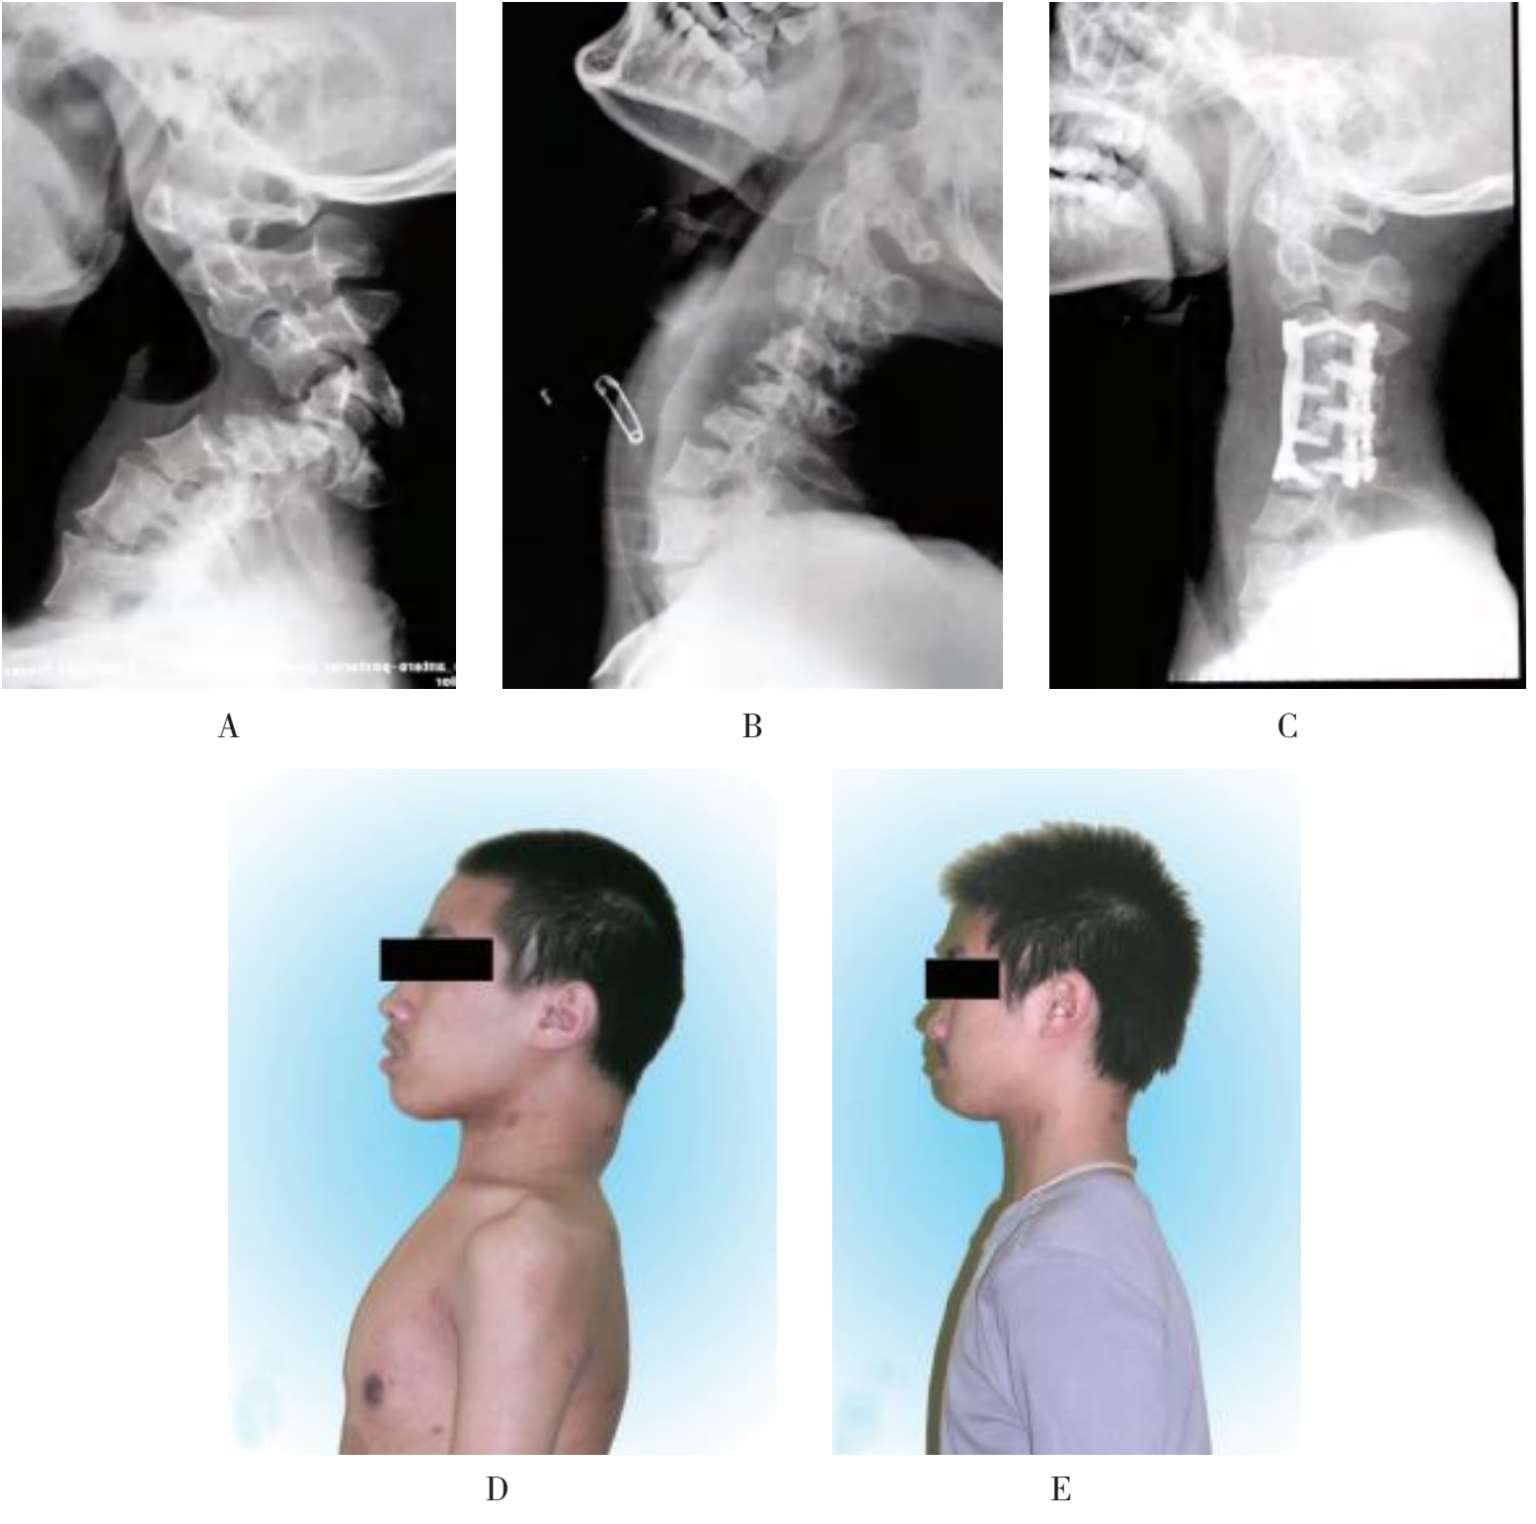

(2)例2:男性,18岁,继发于神经纤维瘤病Ⅰ型的颈椎角状后凸畸形,治疗前C 3 ~C 6 后凸角125°(图1-51A),JOA评分为5分;颈椎悬吊牵引后C 3 ~C 6 后凸角27°(图1-51B);颈椎融合固定手术后C 3 ~C 6 后凸角30°(图1-51C);术前外观侧位,颈部后凸,胸椎代偿性前凸(图1-51D);术后3个月复查时,侧位外观大体像显示颈椎后凸消失,代偿性的胸椎前凸也消失(图1-51E)。

A.治疗前;B.颈椎悬吊牵引后;C.颈椎融合固定术后;D.术前外观侧位;E.术后外观侧位

图1-51 继发于神经纤维瘤病Ⅰ型的颈椎角状后凸畸形